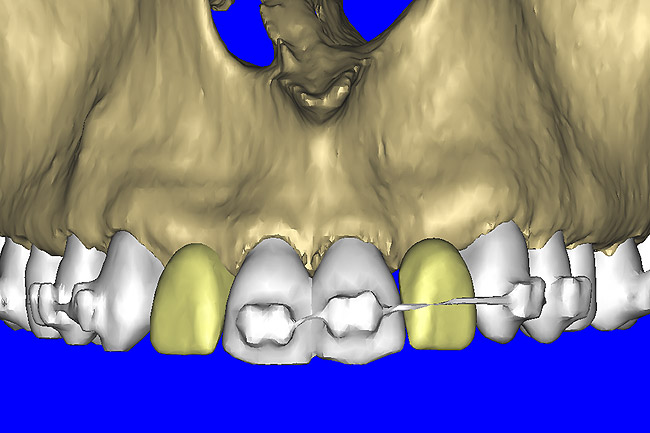

After the basic plan had been established, it was re-evaluated using interactive 3D images. The reconstructed 3D view of the maxilla clearly illustrated the extent of the bilateral facial concavities, and the root eminences of the adjacent and posterior teeth (Figure 7A). The placement of the virtual implants then was evaluated to ensure that the facial cortical plate was not perforated (Figure 7B). The implants were labeled individually as “7” and “10,” with the simulated yellow abutment projection indicating the facial-lingual inclination through the bone to the level above the incisal edge of adjacent teeth. The ability to gain a better understanding of these individual root forms can not be underestimated. The dental literature has suggested certain parameters for placing implants near teeth and implants next to other implants. However, there is little scientific 3D documentation to support these suggested rules.5-10 The use of an interactive treatment-planning software application permits closer scrutiny of previously difficult-to-visualize areas, and can now be used to redefine perceptions of spatial positioning of implants, especially when in close proximity to natural tooth roots, vital anatomy, and adjacent implants.27-29

Using different masking (segmentation) and threshold Hounsfield unit values, several new 3D bone volumes can be created which offer invaluable information. To help determine the final position of each implant a new bone model was created with a Hounsfield unit value of 1480, which eliminated all but the densest objects included in the scan data. (Results may vary depending on the CBCT machine used.) The inner and outer layers of bone were removed, leaving the underlying enamel and root structure of the teeth (Figure 8A). After the bone had been stripped away, the root inclinations were examined closely. The most striking findings confirmed the rotated position of the right central, while revealing the slight mesial dilaceration of the root apex, which converged on the space needed for the path of the potential implant (Figure 8B). The schematic shapes of the proposed implants were visualized for the right and left lateral spaces in different rotations of the 3D maxillary arch. It was at this point that a determination was made as to the appropriate implant shape and type that would fit the available space while avoiding encroachment on adjacent tooth roots. A tapered design implant (Tapered Screw-Vent®, Zimmer Dental, www.zimmerdental.com) was chosen from the large virtual library. With the SIMPlant software, the virtual library contains data from dozens of implant manufacturers and realistic.computer-aided design representations as seen in Figure 9A through the translucent bone. The position of the left implant can be visualized with adequate mesial-distal distance between adjacent tooth roots (Figure 9B) and a more delicate placement (Figure 9C).

Figure 7a  The 3D reconstruction showed (A) the facial concavities and root eminences, and allowed (B) for evaluation of virtual implant placement to ensure the facial cortical plate was not perforated.

Figure 7a

Figure 7b  The 3D reconstruction showed (A) the facial concavities and root eminences, and allowed (B) for evaluation of virtual implant placement to ensure the facial cortical plate was not perforated.

Figure 7b